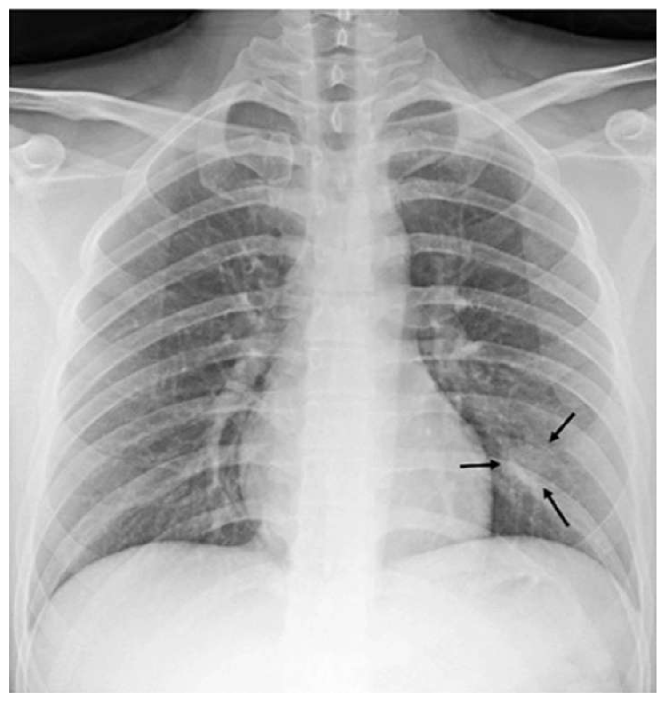

The most common imaging technique used as the first clinical step for chest-related diseases is CXR [26]. Hence, more CXRs could be collected publicly than CT images. A batch of randomly selected samples from the dataset with frontal view, also known as anteroposterior (AP) or posteroanterior (PA), is shown in Fig. 1.

Figure 1: Randomly selected frontal CXR images from different sources